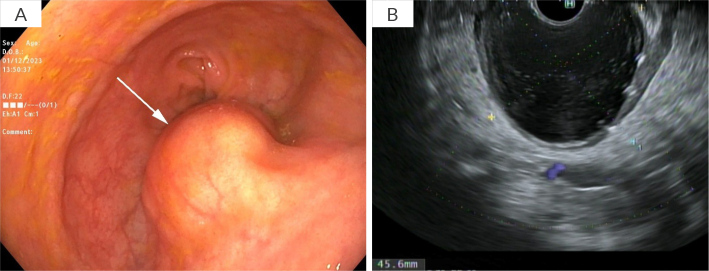

结直肠黏液囊肿是一种罕见的发生在胃肠道的黏液囊肿,对诊断和治疗提出了挑战。我们报告了首例使用腔内金属支架(LAMS)成功治疗腔外结直肠黏液囊肿的病例。65岁男性,既往有憩室炎病史,行部分结肠切除术后出现便秘和腰痛。计算机断层扫描(CT)显示直肠吻合口附近有一个5.4厘米的囊性结构。超声内镜(EUS)发现上皮下病变呈“洋葱皮”状,吸痰细胞学证实为结肠-结肠粘液囊肿。处理包括eus引导放置8 × 8 mm LAMS,允许引流,冲洗和吸痰腔。在2年的随访期间,完全解决,无复发。本病例证明了先进的内镜技术,特别是LAMS在治疗腔外结直肠粘液囊肿方面的潜力。虽然需要进一步的研究来比较LAMS与其他治疗方式的疗效,但该程序为某些患者提供了手术的微创替代方案。学习要点:一种治疗罕见的结肠黏液囊肿的新方法,使用顺腔金属支架。

Colorectal mucoceles are rare mucinous cysts arising in the gastrointestinal tract and presenting diagnostic and therapeutic challenges. We report the first successful treatment of an extraluminal colorectal mucocele using a lumen-apposing metal stent (LAMS). A 65-year-old male with a known medical history of diverticulitis treated with a partial colectomy presented with constipation and low back pain. Computed tomography scan (CT) revealed a 5.4 cm cystic structure adjacent to the rectal anastomosis. Endoscopic ultrasound (EUS) found a subepithelial lesion with an "onion peel" appearance, and aspiration cytology confirmed a colo-colonic mucocele. Management consisted of EUS-guided placement of an 8 × 8 mm LAMS, allowing for drainage, irrigation, and suctioning of the cavity. Complete resolution was achieved without recurrence over a 2-year follow-up period. This case demonstrates the potential of advanced endoscopic techniques, particularly LAMS, in managing extraluminal colorectal mucoceles. While further research is needed to compare the efficacy of LAMS with other treatment modalities, this procedure offers a minimally invasive alternative to surgery for certain patients.